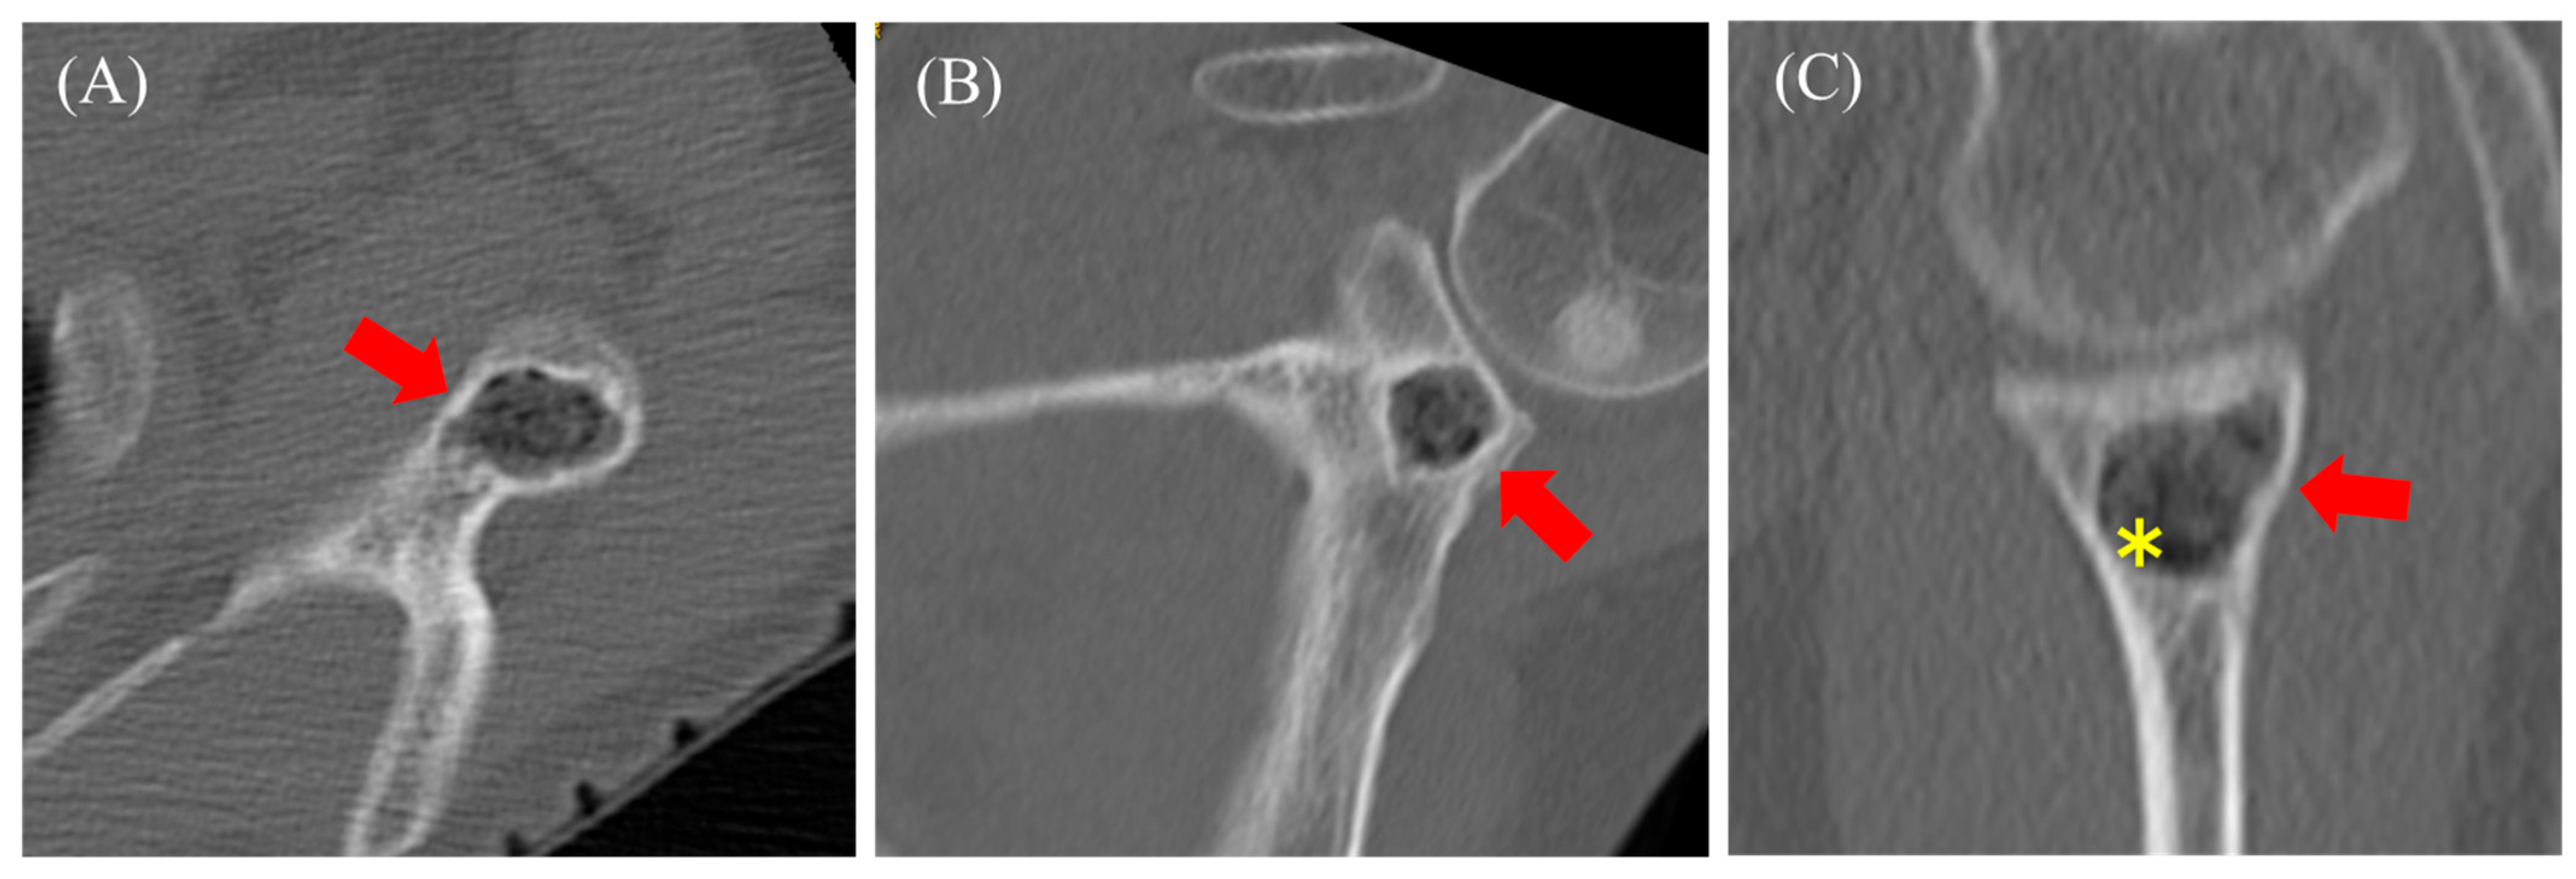

2.2. Case 2